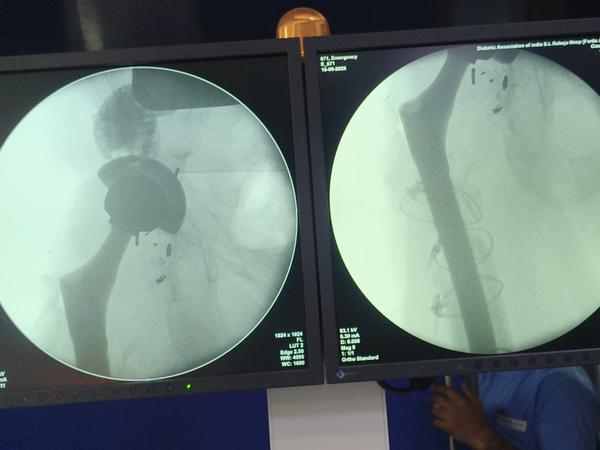

Dr Ajay Randive : IS MS Ortho (Mumbai) MRCSI ( UK) Consultant knee, Hip ,& Spine Surgeon, Dr Ajay Randhive is a eminent Knee, Hip , & Spine Surgeon practicing in to areas Andheri East,Santacruz East. Dr Ajay Randive did his MS Ortho residency from LTMMC, Sion Hospital Mumbai. He did overseas training in UK from 2003 till 2008. He is trained in total Knee Replacement, Hip Replacement, Revision Hip Replacement And Revision Knee Replacement Surgeries. He has worked at The Royal London Hospital. IN London where he worked a clinical fellow in joint Replacement unit. He has carried out more than 5000 Knee Replacement surgeries, 2500 Hip Replacement Surgeries, More Than 500 Revison Knee And Hip Replacement Surgeries 600 Spine surgeries & more than 1500 arthroscopic surgeries (Knee & Shoulder).